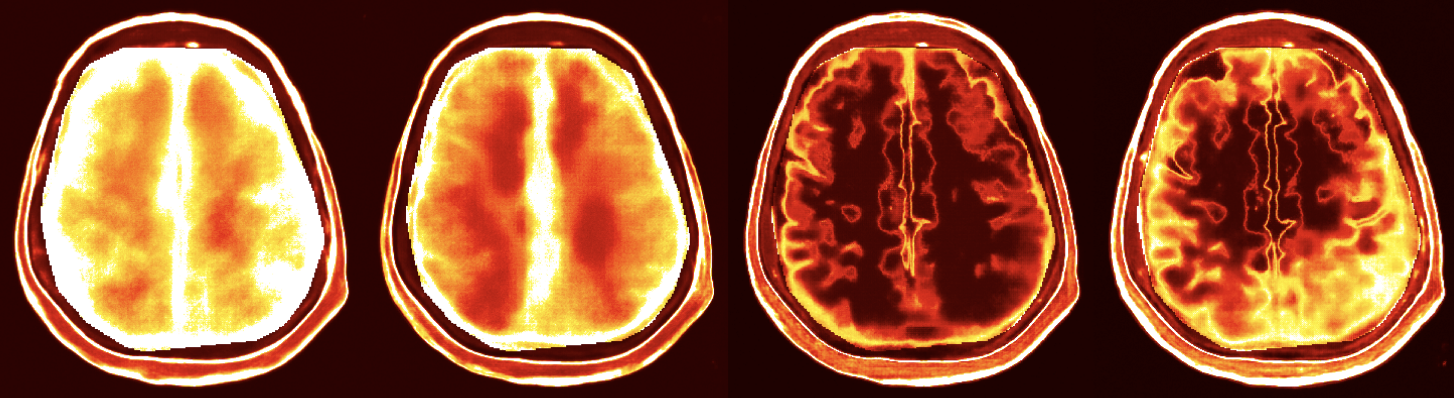

…and various medical imaging modalities including X-ray CT

Full waveform inversion with ultrasound for intracranial imaging

“ASPIRE: Iterative Amortized Posterior Inference for Bayesian Inverse Problems”